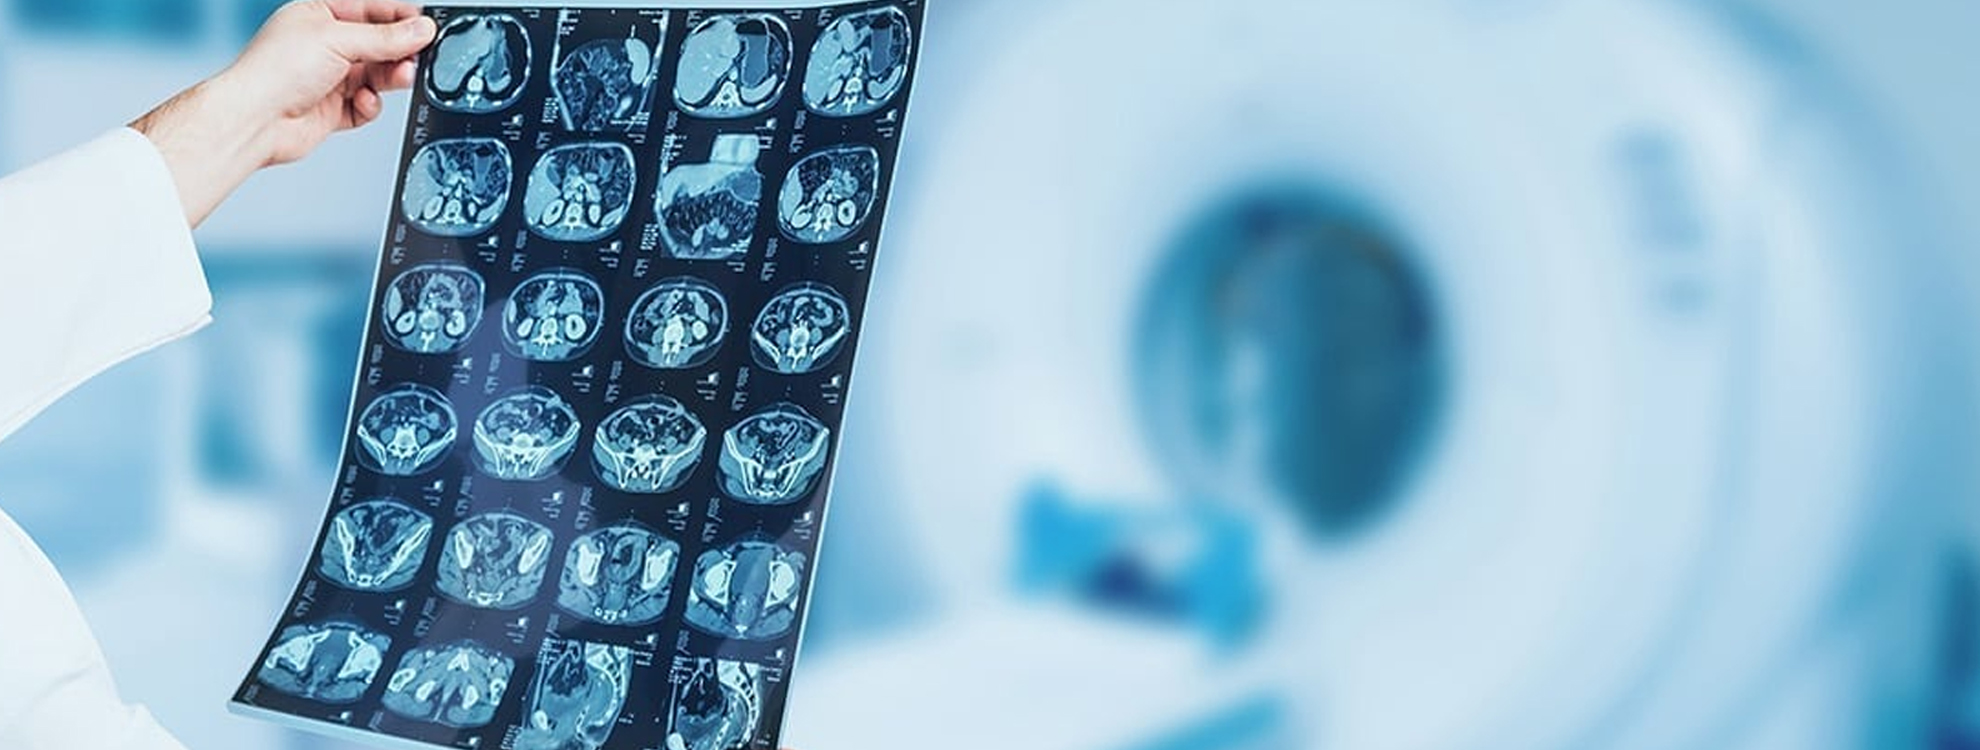

Indian Radiological & Imaging Association of Karnataka state chapter is a registered organization of Radiologists.

Objectives of the association are academic enhancement, research support, education to residents and radiologists, welfare of its members, and supporting societal needs and concerns.

IR & IA is promoting the study and practice of diagnostic radiological and imaging modalities including X-ray, Ultrasound, C.T., M.R.I., Interventional Radiology, and other related subspecialties/super-specialties.

IRIA actively holds periodical meetings, CME programmes, clinical webinars, and conferences on related sub-specialties/super-specialties at various subchapters and institutions, both offline and online.